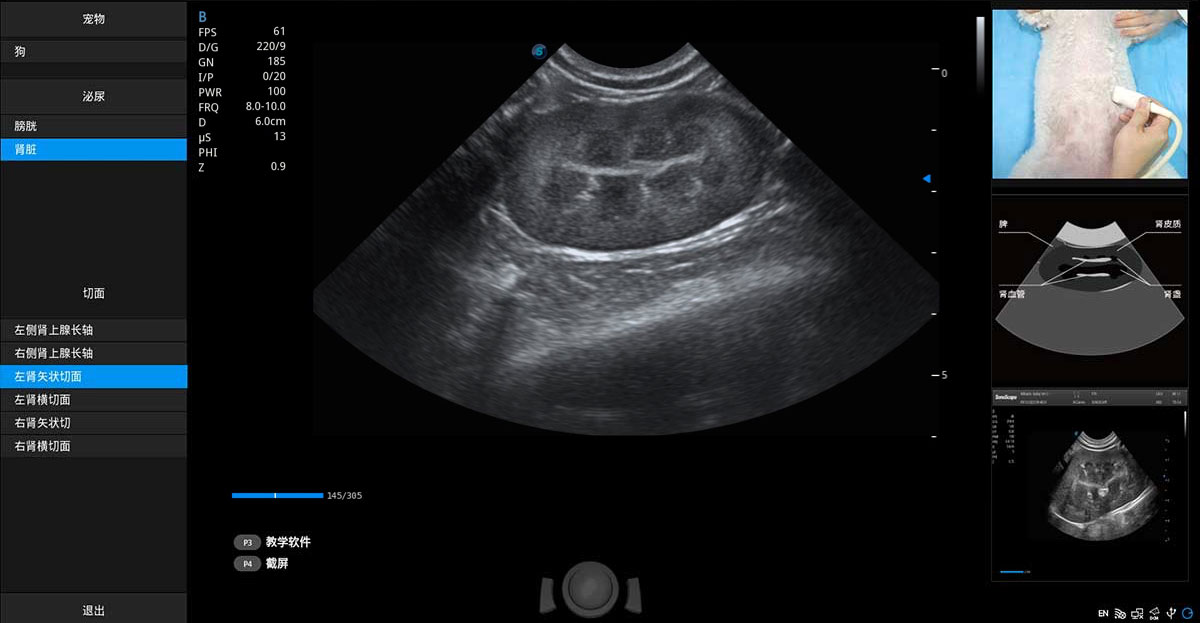

提供解剖示意圖、標(biāo)準(zhǔn)超聲圖像、掃查手法涂和操作者實(shí)時檢查圖像,指導(dǎo)操作者進(jìn)行標(biāo)準(zhǔn)切面的正確掃查。

ProPet 80 專為動物醫(yī)生設(shè)計,對不同的動物體型和生理結(jié)構(gòu)作出了針對性的優(yōu)化。通過動物影像專用軟件,可滿足個性化的應(yīng)用需求,幫助動物醫(yī)生獲得更精確的診斷數(shù)據(jù)。